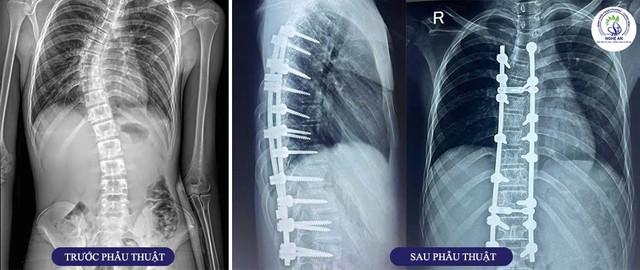

Hình ảnh phim Xquang trước và sau phẫu thuật của bệnh nhân 16 tuổi mắc vẹo cột sống vô căn.

Bệnh nhân nam 16 tuổi, quê ở Thanh Chương – Nghệ An được chẩn đoán vẹo cột sống ngực – thắt lưng vô căn tuổi thiếu niên (AIS), với các chỉ số: góc vẹo Cobb 45 độ, Risser độ IV – giai đoạn phát triển xương gần hoàn tất. Biến dạng ảnh hưởng đến tư thế, thẩm mỹ và tiềm ẩn nguy cơ chèn ép thần kinh, giảm dung tích sống phổi nếu không được can thiệp kịp thời.

Ca phẫu thuật do BSCKII Nguyễn Hoàng Dương – Trưởng khoa Phẫu thuật Thần kinh – Sọ não – Cột sống trực tiếp chỉ đạo và thực hiện cùng ê-kíp. Phẫu thuật được thực hiện qua đường sau, với kỹ thuật chỉnh hình và cố định cột sống bằng hệ thống vít – thanh nẹp; bao gồm: 15 vít qua cuống sống vùng ngực – thắt lưng, 2 thanh dọc phục hồi trục giải phẫu, 2 thanh ngang tăng cường ổn định, xương ghép nhân tạo hỗ trợ hàn xương liên bản sống.

Sau phẫu thuật chỉnh hình và cố định cột sống kết hợp tập phục hồi chức năng chuyên sâu tại Bệnh viện Chấn thương Chỉnh hình Nghệ An, cột sống bệnh nhân thẳng trục hơn, gần như hết vẹo; tình trạng đau lưng giảm rõ rệt, sinh hoạt dễ dàng hơn và cải thiện về thẩm mỹ.